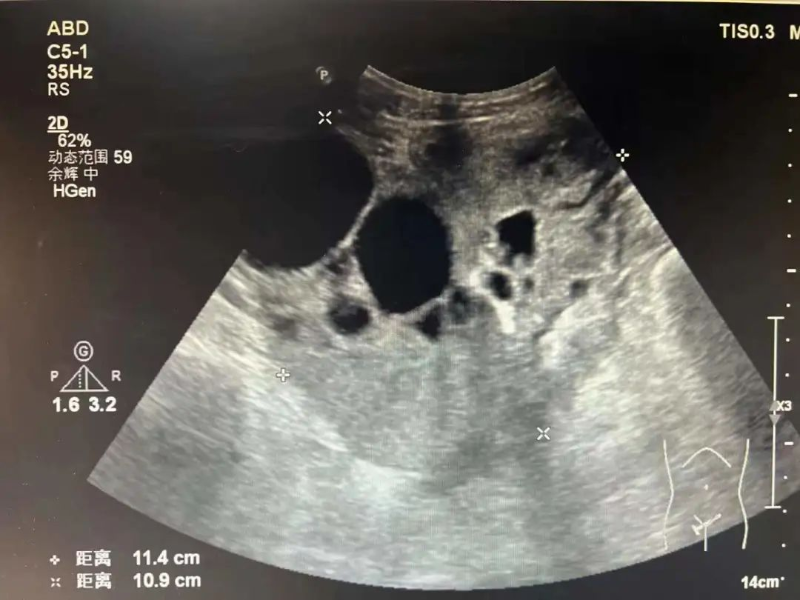

馬女士(化名)因持續三天腹痛、惡心、精神欠佳、食欲不振、體力下降,于是到我院就診。急診值班醫生檢查后懷疑是腸梗阻收治入院。3月15日,經胃腸/肝膽/甲狀腺外科專科醫生和婦科醫生的聯合會診,CT檢查發現馬女士盆腔兩側似見多發團片混雜密度影,脾胃似見團塊影,需要進一步檢查診斷。

3月16日,超聲醫學科主任陳勇輝主任醫師為馬女士進行超聲引導卵巢腫瘤穿刺活檢,陳勇輝通過超聲掃描對病變進行精準測量、定位,選擇最佳穿刺點,經過局部麻醉后,用穿刺針切割病變活性組織,送至病理科檢查。經檢查后馬女士確診卵巢漿液性囊性癌,有了超聲醫學科的精準穿刺活檢,為馬女士后續診療打下良好基礎。